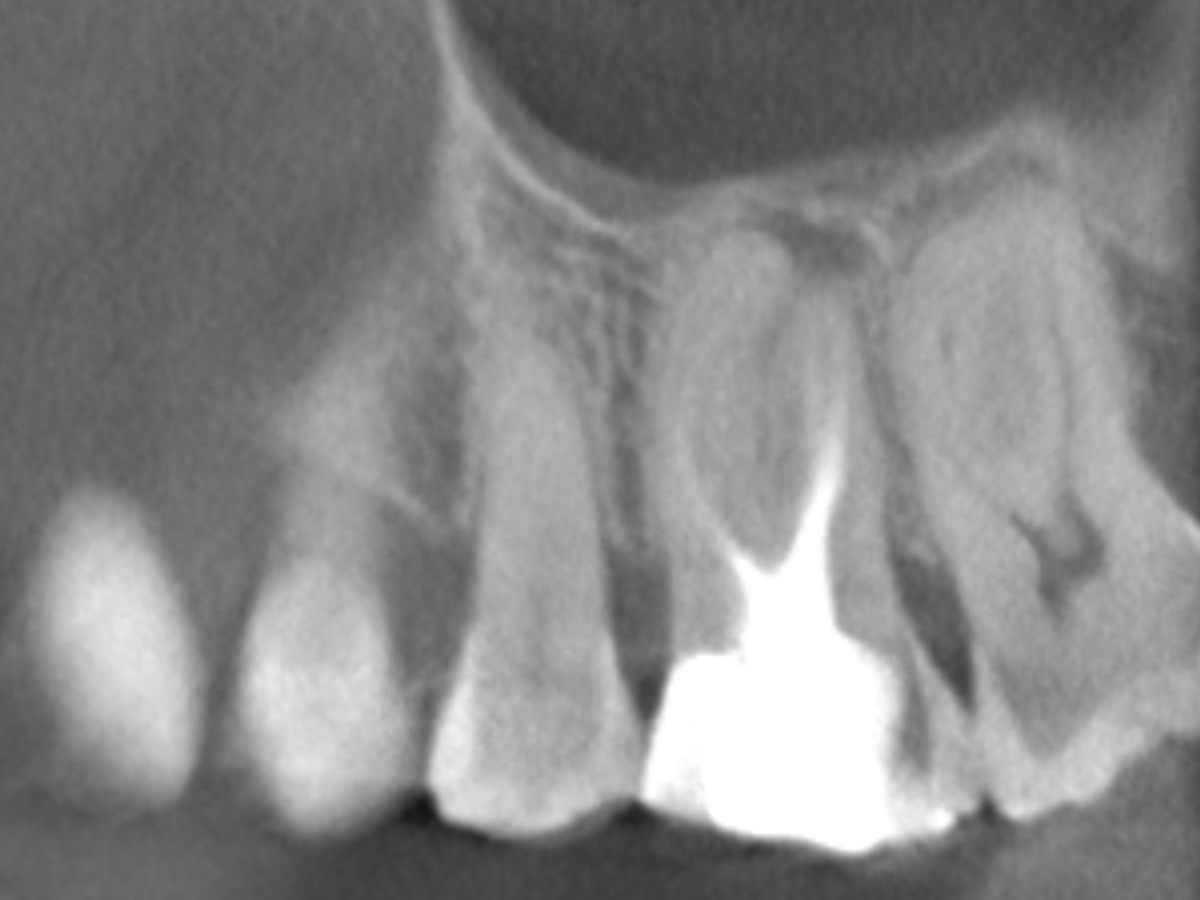

Obturation nach einer erfolgreichen Revision der insuffizienten Wurzelkanalfüllung mit einer symptomatischen apikalen Parodontitis

Der Patient stellte sich mit Aufbissschmerzen vor, wobei die klinische und röntgenologische Untersuchung eine symptomatische apikale Parodontitis an einem bereits wurzelkanalbehandelten Zahn 26 ergab. Die DVT-Aufnahme deutete auf einen unbehandelten zusätzlichen Kanal in der mesio-bukkalen Wurzel hin. Die Darstellung und Behandlung des mb2s sowie die Revision der bereits behandelten Kanäle erfolgte mit dem XP-endo® Rise Shaper bei einer hohen Umdrehungszahl von 2.500rpm.

Abbildung 3

DVT sagittal